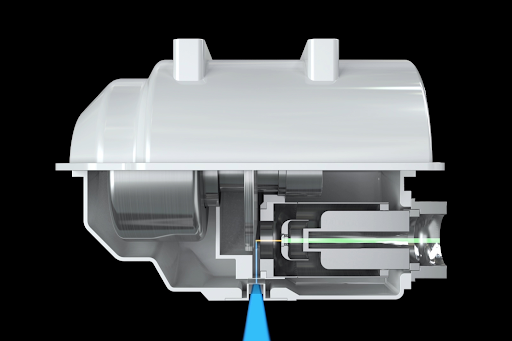

CANON AQUILION PRECISION — это первая в мире система для проведения КТ сверхвысокого разрешения (UHR CT), способная визуализировать изображения с точностью до 150 микрон. Детектор UHR был разработан для обеспечения более чем вдвое более высокого разрешения по сравнению с современной технологией КТ, с совершенно новым детектором, а также с трубками, гентри и технологиями реконструкции.

Aquilion Precision представляет собой инновационный подход к реконструкции изображений, использующий нейронные сети AiCE, специально обученные выполнять одну задачу - восстанавливать четкие изображения. Нейронная сеть обучена использованию усовершенствованного алгоритма итеративной реконструкции на основе моделей (MBIR) для получения изображений с низким уровнем шума и КТ со сверхвысоким разрешением (матрица 1024).

Инновации в реконструкции изображений:

- Новая матрица, 1024 х 1024;

- Оптимизировано для КТ UHR;

- 150 микрон, разрешение 50 lp / cm *;

- AIDR 3D ;

- ПЕРВЫЙ (MBIR), оптимизированный для UHR CT